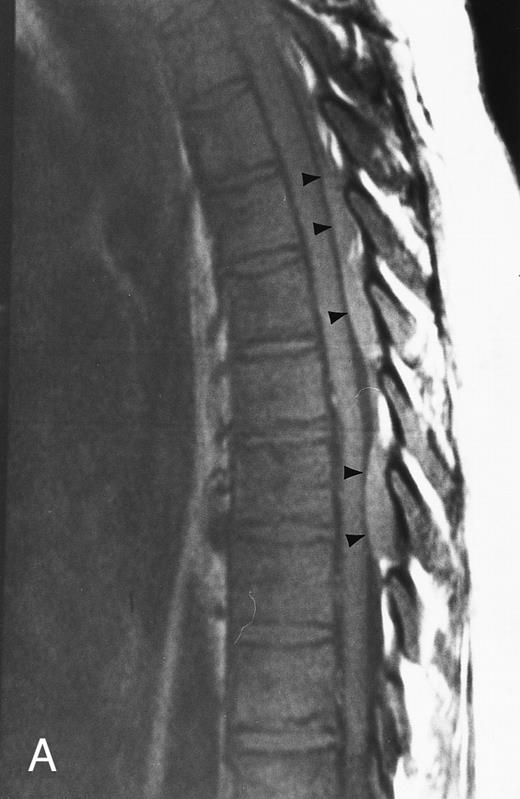

Diffuse MR pattern of abnormal marrow in a 29-year-old man with AML: T1-weighted sagittal (500/10, TR/TE) (A), T2-weighted, fat-suppressed fast spin echo sagittal (5000/96, TR/TE, ET 16) (B), and enhanced T1-weighted sagittal (500/10, TR/TE) (C) MR images of the thoracic spine. The abnormal vertebral bodies in (A) are dark and isointense to the intervertebral discs and in (B) they become bright. In (C), the abnormal marrow enhances and the vertebrae become brighter than the discs. Note extraosseous mass (arrowheads) in the posterior epidural space with preservation of the bony cortex.